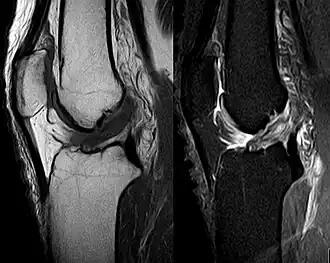

MRI shows normal signal of both cruciate ligaments (arrows)

MRI shows normal signal of both cruciate ligaments (arrows) -